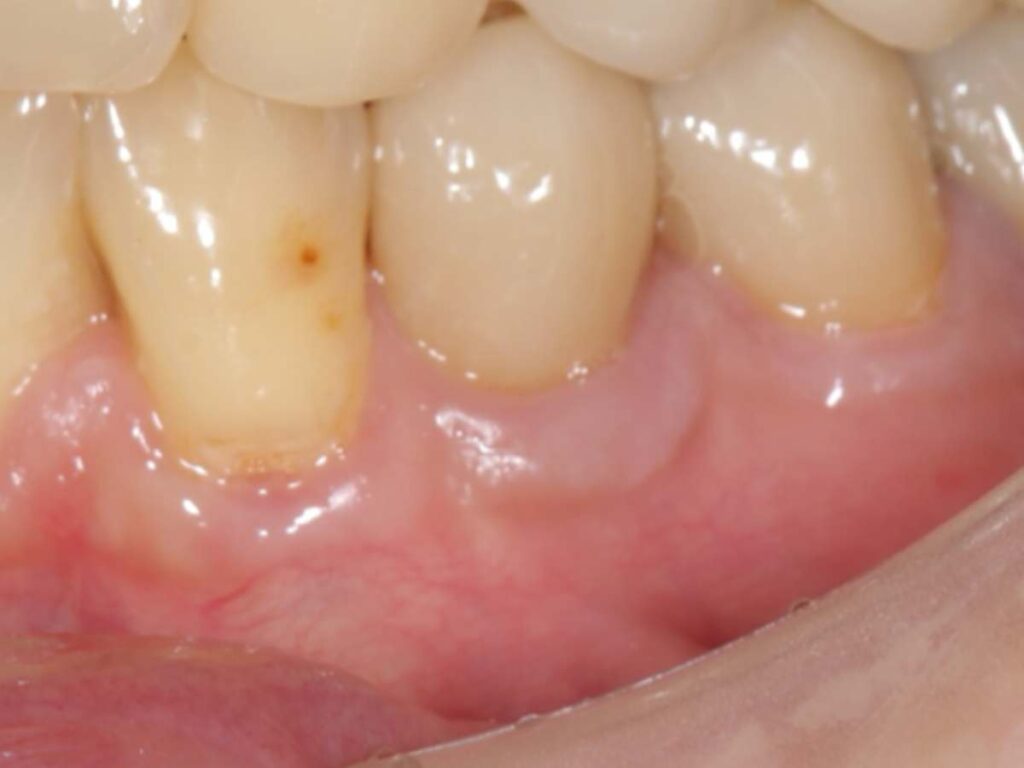

- 術後側方面観(術後10年以上経過)

- 術後正面観(術後10年以上経過)

この方法により、単に虫歯を治すだけでなく歯根の露出を改善、歯ぐきの厚みを回復、再び虫歯になりにくい環境を作るという根本的な改善を目指しました。

結果として、術後10年以上経過しても歯肉は安定しており、根元の虫歯の再発も認めていません。